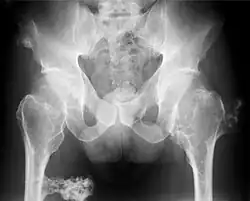

Multiple Osteochondrome im Beckenbereich, Röntgenaufnahme

Multiple kartilaginäre Exostosen ist die Bezeichnung für eine autosomal-dominant vererbte Erkrankung mit zahlreichen gutartigen knorpelbedeckten Knochentumoren. Da es sich um Osteochondrome handelt, die mit hyalinem Knorpel statt Faserknorpel bedeckt sind, ist die Bezeichnung „kartilaginäre“ Exostose eigentlich nicht korrekt.[1] Mit einer Inzidenz von etwa 1:50.000 zählt die Exostosenkrankheit zu den häufigsten Knochentumorerkrankungen,[2] Frauen und Männer sind gleich häufig betroffen. Bei etwa 70 % der Patienten liegt eine familiäre Form vor, etwa 30 % haben eine sporadische Form, also eine Neumutation.

Zum Zeitpunkt der Geburt sind Exostosen noch sehr selten, sie entstehen vor allem in der Kindheit und Jugend, bis zum Schluss der Wachstumsfugen. In dieser Zeit nehmen die Exostosen auch an Größe zu. Nach Ende des Wachstums bilden sich keine weiteren Exostosen, und eine spätere Größenzunahme ist dann ein Zeichen einer malignen Transformation (Entartung), d. h. Umwandlung in einen bösartigen Knochentumor. In etwa 3 – 5 % tritt ein sekundäres Chondrosarkom auf.